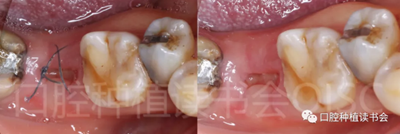

圖1 無法保留的上頜隱裂后牙,拔牙后即刻種植。

患者為70歲女性,右下后牙樁核冠因遠(yuǎn)中牙根縱裂脫落,全身健康狀況良好,輕度骨質(zhì)疏松??趦?nèi)檢查:47殘根,遠(yuǎn)中根縱裂,部分根面已腐至齦下2mm,叩(++),松(-);48近中傾斜阻生,咬合關(guān)系、修復(fù)間隙及牙周情況正常(圖12)。

圖12 遠(yuǎn)中根縱裂及根面齲導(dǎo)致47殘根無法保留。